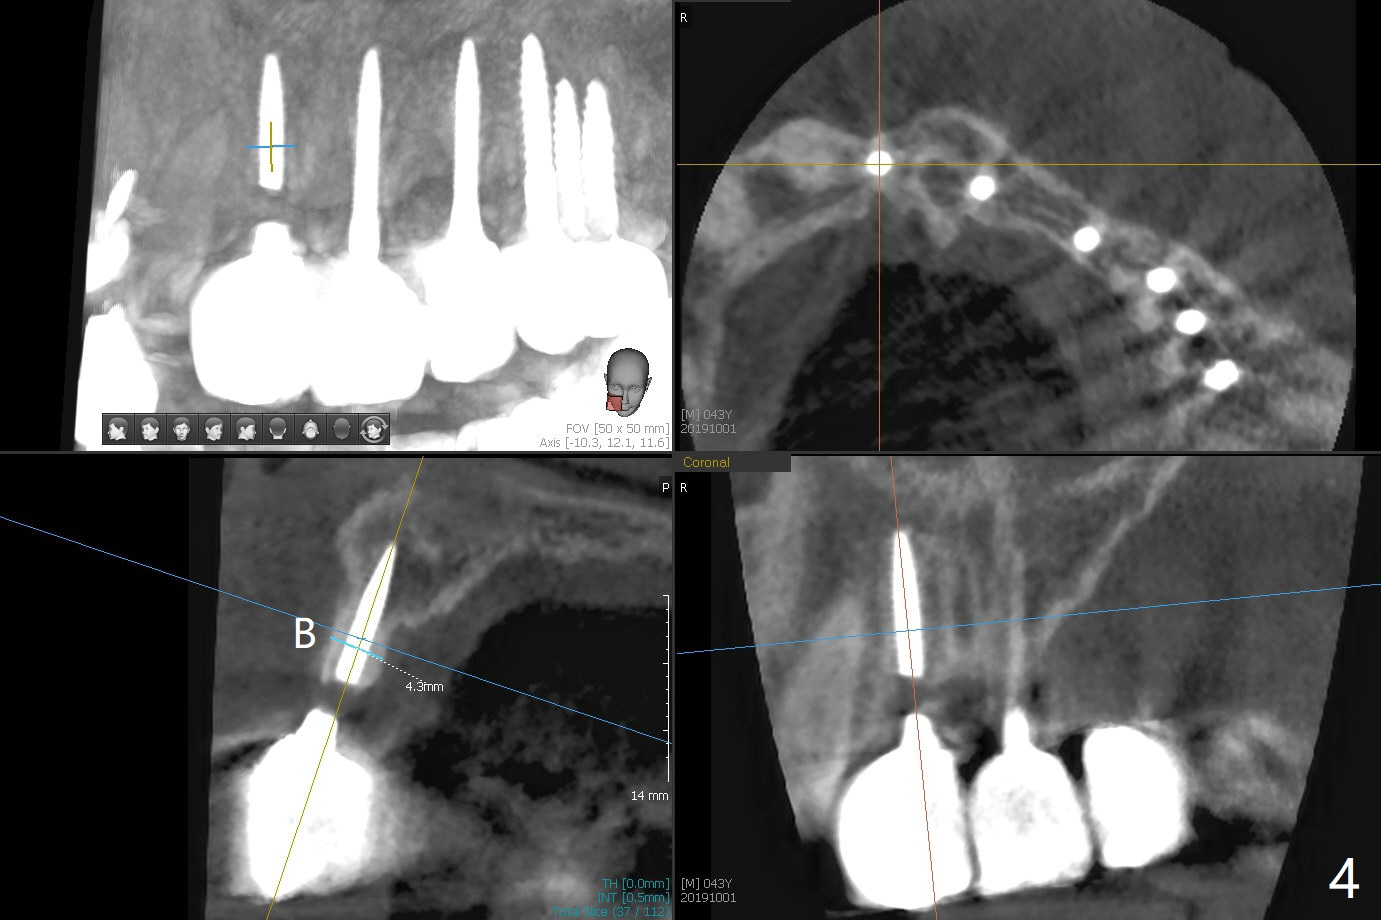

The ridge is wide enough for a 3.5x10 mm

implant (Fig.16 (CT taken when #8 implant fractured)). Return to Upper Incisor Immediate Implant, Trajectory II 1-Piece Prevent Fracture Xin Wei, DDS, PhD, MS 1st edition 10/01/2019, last revision 06/12/2020 |

A 43-year-old man has 6 of 1-piece implants in the maxilla (#8-13). His daughter's head hits his upper anterior teeth 7 months post cementation. Exam shows that the tooth #7 has mild percussion. Nine months later the implant crown at #8 becomes displaced and loose when he bites apple (Fig.1 arrow). Forceps are used to remove the crown, leaving a concave implant site (Fig.2). After the crown is bonded to the neighboring tooth/implant crown (Fig.3 *), the patient feels pain from the neighboring tooth. The alveolus is 4.3 mm wide (Fig.4 (2.9 mm preop)), allowing 2.5 or 3.0 mm immediate implant re-placement (Fig.5). A 2.0/3.0 mm trephine bur will be used for implant removal. Try to place the new implant slightly distal to improve the trajectory (Fig.6). Particulate and/or onlay graft is an option. Prepare dummy implants. As planned, the fractured implant is removed by using a 2.0/3.0 mm trephine bur following incision (Fig.7). After use of Lindamann bur to remove the distal bone, a 3x14(4) mm dummy implant is placed with 20 Ncm (Fig.8). A longer implant could be used (3x16(2 or 4) mm), but a 3.5x13 mm 1-piece implant is placed with ~ 50 Ncm after use 3.0 mm drill (Fig.9,10). Allograft is placed around the implant (Fig.9,10 *), followed by Amnion-Chorion membrane and 5-0 PGA sutures (Fig.11). Allograft placed around the implant (Fig.9 *) appears to be able to prevent implant thread exposure 4 months postop (Fig.12). PA is taken when the crown is cemented (Fig.13). Four months postop cementation of #8 crown, the patient returns because of #9 mobility (Fig.14). In fact the implant fractures when the loose crown is removed with forceps; there is bone loss at #10. Bone graft will be placed at #10 with sticky bone (PRFx1), while the implant at #9 is redo. The ridge is wide enough for a 3.5x10 mm implant (Fig.16 (CT taken when #8 implant fractured)). Also prepare Tatum angled 1-piece implant. The 2 mm implant is too thin when occlusion contact at #10-13 is incomplete. The crowns will be redone when the implant at #9 is osteointegrated.